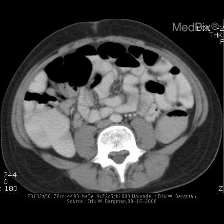

Medicine is inherently multimodal, with rich data modalities spanning text, imaging, genomics, and more. Generalist biomedical artificial intelligence (AI) systems that flexibly encode, integrate, and interpret this data at scale can potentially enable impactful applications ranging from scientific discovery to care delivery. To enable the development of these models, we first curate MultiMedBench, a new multimodal biomedical benchmark. MultiMedBench encompasses 14 diverse tasks such as medical question answering, mammography and dermatology image interpretation, radiology report generation and summarization, and genomic variant calling. We then introduce Med-PaLM Multimodal (Med-PaLM M), our proof of concept for a generalist biomedical AI system. Med-PaLM M is a large multimodal generative model that flexibly encodes and interprets biomedical data including clinical language, imaging, and genomics with the same set of model weights. Med-PaLM M reaches performance competitive with or exceeding the state of the art on all MultiMedBench tasks, often surpassing specialist models by a wide margin. We also report examples of zero-shot generalization to novel medical concepts and tasks, positive transfer learning across tasks, and emergent zero-shot medical reasoning. To further probe the capabilities and limitations of Med-PaLM M, we conduct a radiologist evaluation of model-generated (and human) chest X-ray reports and observe encouraging performance across model scales. In a side-by-side ranking on 246 retrospective chest X-rays, clinicians express a pairwise preference for Med-PaLM M reports over those produced by radiologists in up to 40.50% of cases, suggesting potential clinical utility. While considerable work is needed to validate these models in real-world use cases, our results represent a milestone towards the development of generalist biomedical AI systems.

In this work, we detail our progress towards such a generalist biomedical AI system - a unified model that can interpret multiple biomedical data modalities and handle many downstream tasks with the same set of model weights. One of the key challenges of this goal has been the absence of comprehensive multimodal medical benchmarks. To address this unmet need, we curate MultiMedBench, an open source multimodal medical benchmark spanning language, medical imaging, and genomics modalities with 14 diverse biomedical tasks including question answering, visual question answering, medical image classification, radiology report generation and summarization, and genomic variant calling.

We next describe MultiMedBench, a benchmark we curated to enable the development and evaluation of generalist biomedical AI. MultiMedBench is a multi-task, multimodal benchmark comprising 12 de-identified open source datasets and 14 individual tasks. It measures the capability of a general-purpose biomedical AI to perform a variety of clinically-relevant tasks. The benchmark covers a wide range of data sources including medical questions, radiology reports, pathology, dermatology, chest X-ray, mammography, and genomics. Tasks in MultiMedBench vary across the following axes:

Modality: text, radiology (CT, MRI, and X-ray), pathology, dermatology, mammography, and genomics.